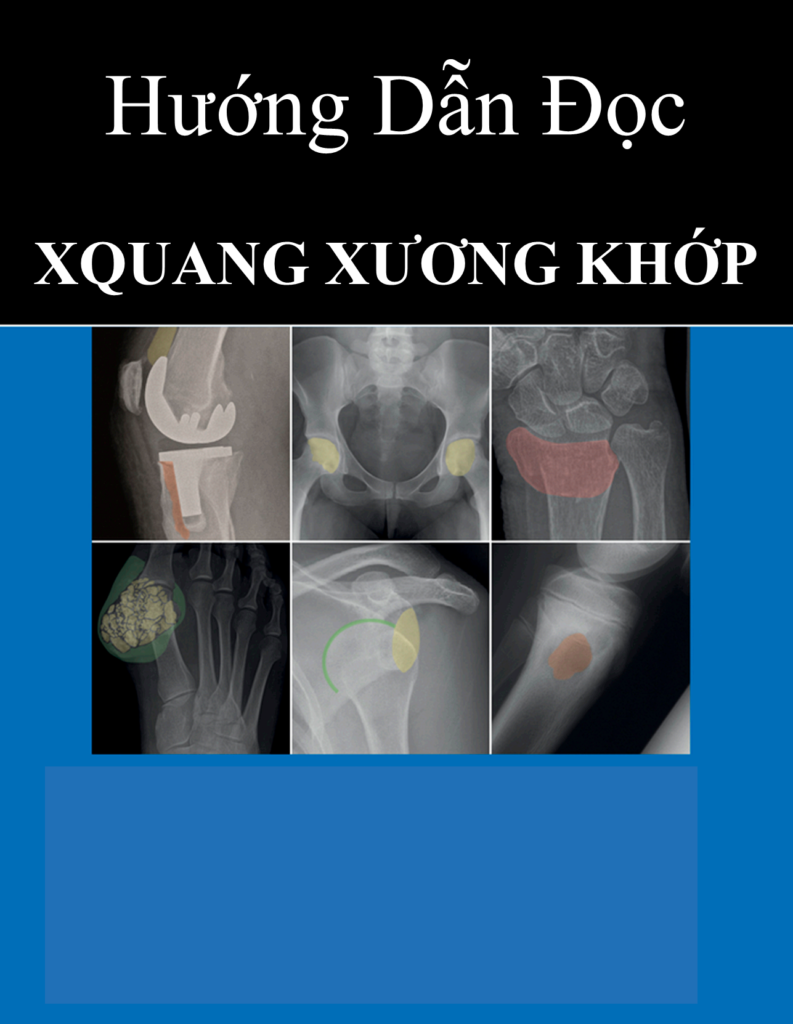

Hôm nay, Trang vừa sưu tầm được một tài liệu hay về chẩn đoán hình ảnh và X-quang nên muốn chia sẻ đến các bạn để chúng ta cùng nhau tham khảo nhé. Tài liệu “Hướng Dẫn Đọc XQuang Cơ Xương Khớp”. Quyển sách dịch được biên soạn khá đầy đủ, dịch thuật từ quyển […]